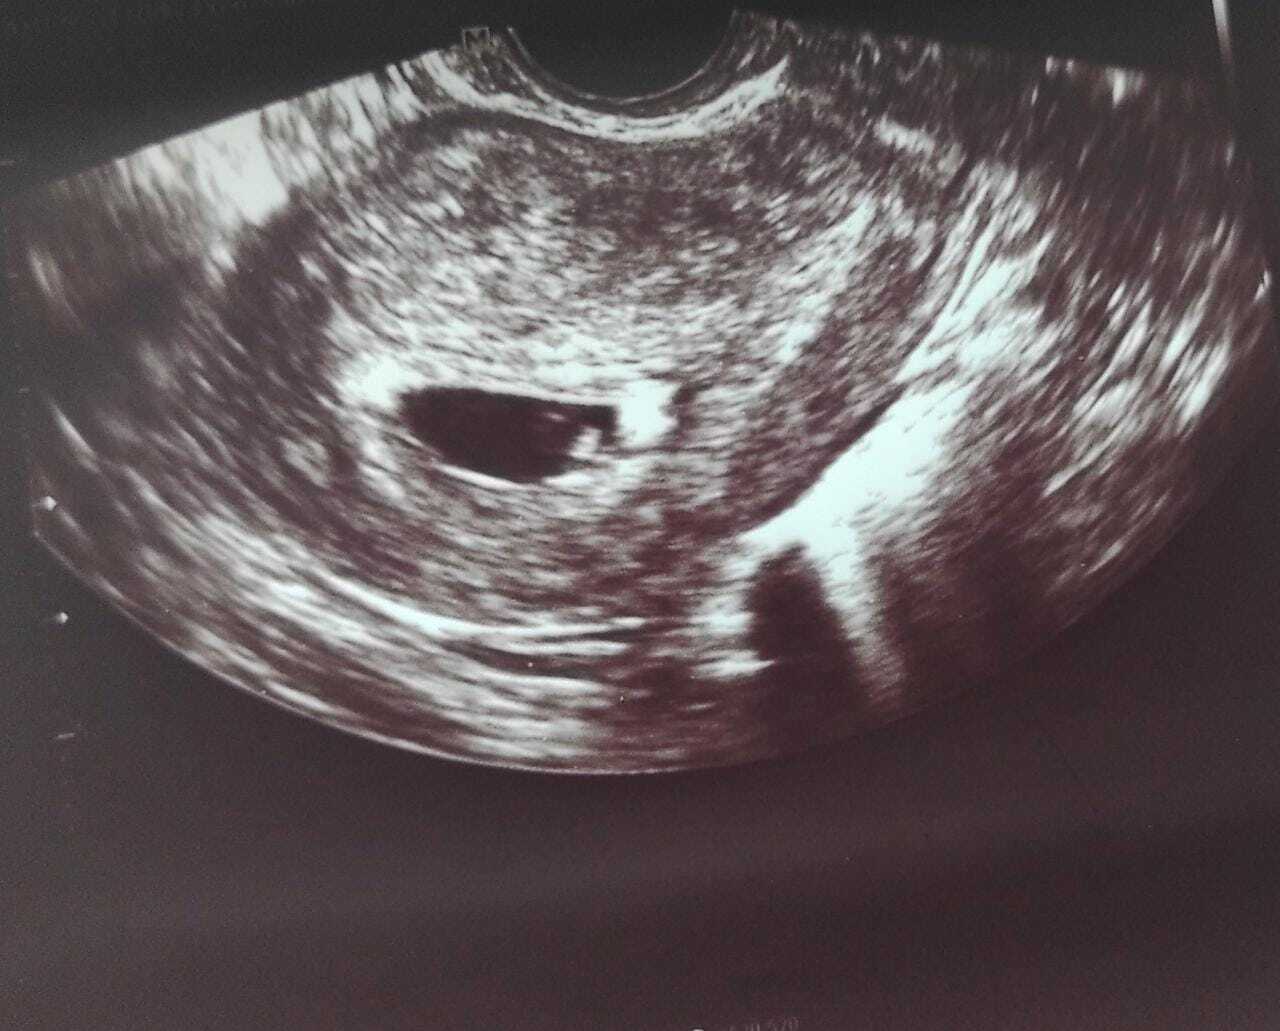

ULTRASON